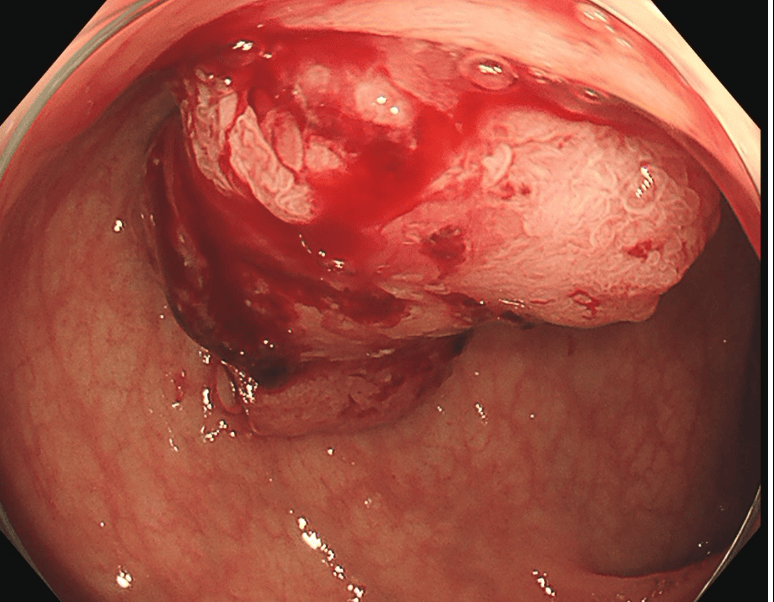

大腸がんに対してTNT療法を行った例

治療後